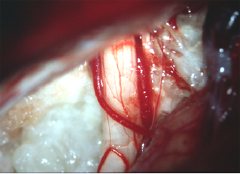

小脳橋角部の典型的な類表皮のう胞 epidermoid cyst

60代の女性の手術中の写真です。この女性も三叉神経痛で発症した小脳橋角部の類表皮のう胞です。左の写真で,白く光って真珠のように見えるの (pearly tumor) が腫瘍です。右側は腫瘍を全部とり終えた後の写真です。三叉神経の真ん中が凹んでいました。この患者さんも症状は消えて再発はしていません。でも,三叉神経痛で発症した患者さんの治療は必ずしも容易ではありません。